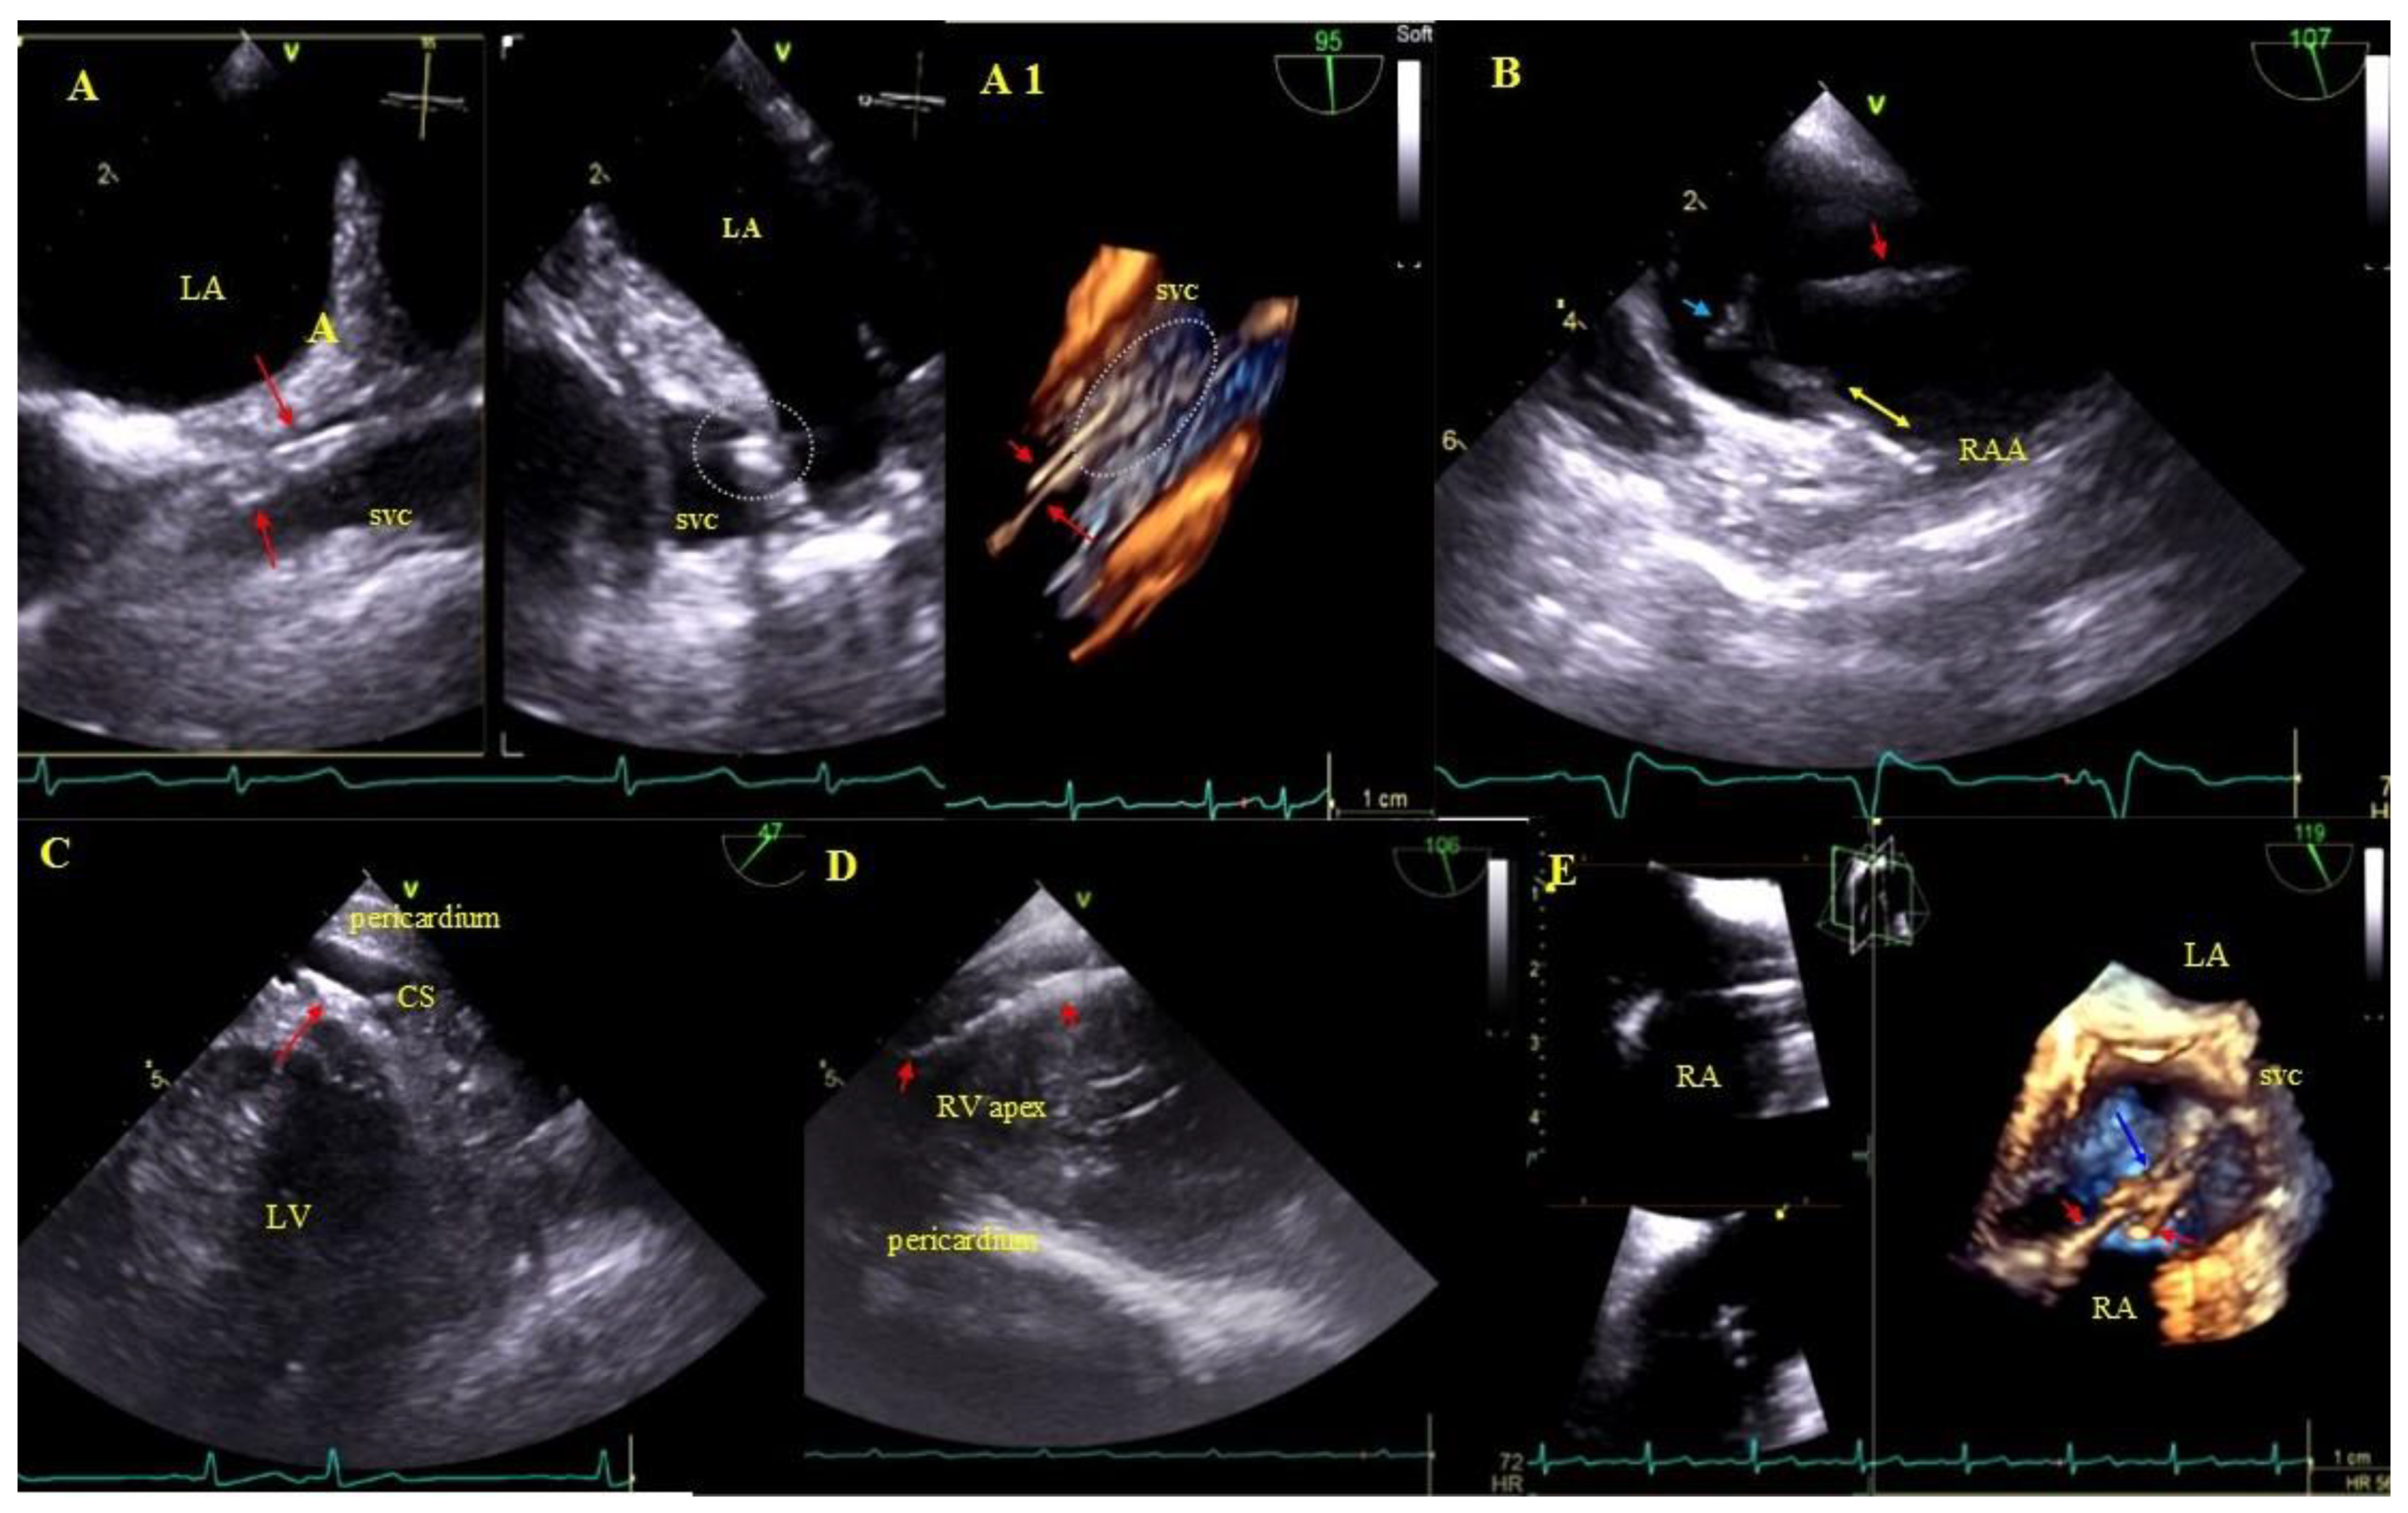

2.5. Echocardiographic Findings Associated with Endocardial Leads: Definition and Classification According to the Anatomy and Characteristic Features